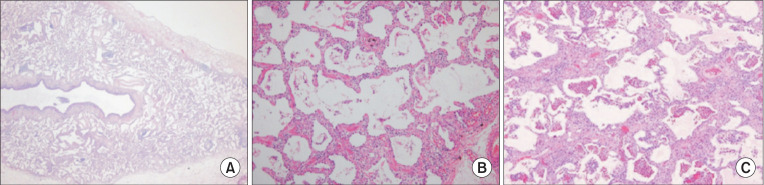

Idiopathic nonspecific interstitial pneumonia (iNSIP) is recognized as a distinct entity among various types of idiopathic interstitial pneumonias. It is identified histologically by the nonspecific interstitial pneumonia pattern. A diagnosis of iNSIP is feasible once secondary causes or underlying diseases are ruled out. Usually presenting with respiratory symptoms such as shortness of breath and cough, iNSIP has a subacute or chronic course. It predominantly affects females aged 50 to 60 years who are non-smokers. Key imaging findings on chest high-resolution computed tomography include bilateral reticular opacities in lower lungs, traction bronchiectasis, reduced lung volumes and, ground-glass opacities. Abnormalities are typically diffuse across both lungs with subpleural distributions. Treatment often involves systemic steroids, either alone or in combination with other immunosuppressants, although evidence supporting effectiveness of these treatments is limited. Prognosis is generally more favorable for iNSIP than for idiopathic pulmonary fibrosis, with many studies reporting a 5-year survival rate above 70%. Antifibrotic agents should be considered in a condition, termed progressive pulmonary fibrosis, where pulmonary fibrosis progressively worsens.